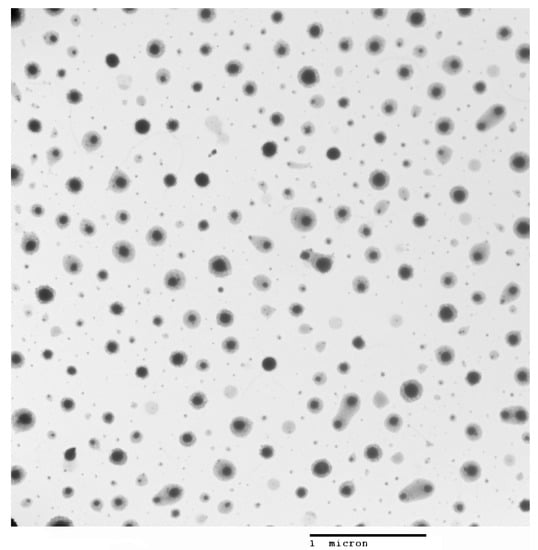

For nanoparticle characterization, particle size and zeta potential were determined using a Zetasizer and a Nanosight NS300 instrument from Malvern Panalytical. Transmission electron microscopy (TEM) was performed using a tungsten filament HV at 100 kV (Hitachi, Tokyo, Japan). Quantification of GSH inside nanoparticles was conducted indirectly via a colorimetric method using 2,2′-dinitro-5-5′dithiodibenzoic acid (DTNB), and the results were determined at a wavelength of 425 nm.

Two sets of chitosan NPs, with and without glutathione, were prepared using the ion gelation method previously described [13]. The results of their characterization are shown in Figure 1 and Figure 2 and Table 2

Figure 2. Transmission electron microscopy of chitosan–glutathione nanoparticles.